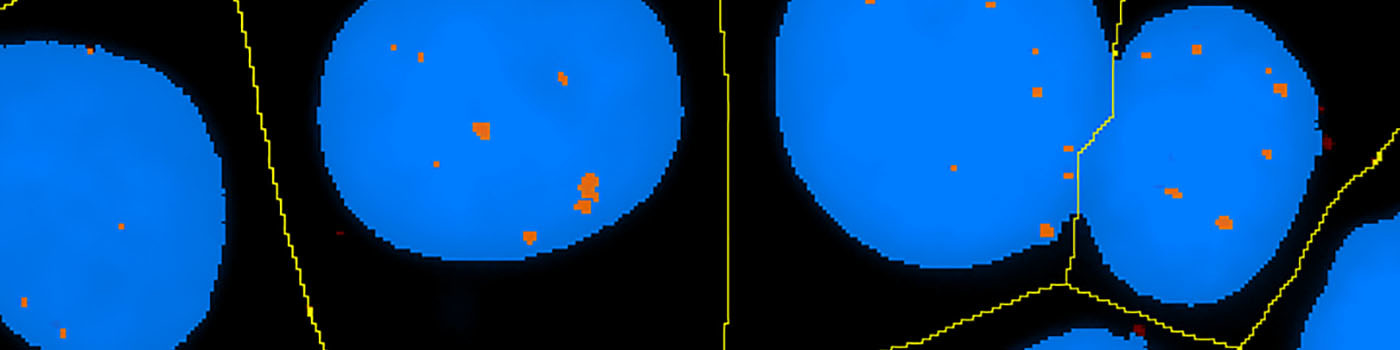

The number of in situ PLA signals per nuclei was counted by automated image analysis. Fully automated nuclei delineation was initiated by identifying cell nuclei using the signal from the nuclear Hoechst staining (blue). Touching nuclei were separated using a combination of distance transformation and watershed segmentation. In situ PLA signals were counted by enhancing point-like signals and defining a true signal as a local intensity maximum above a background threshold.